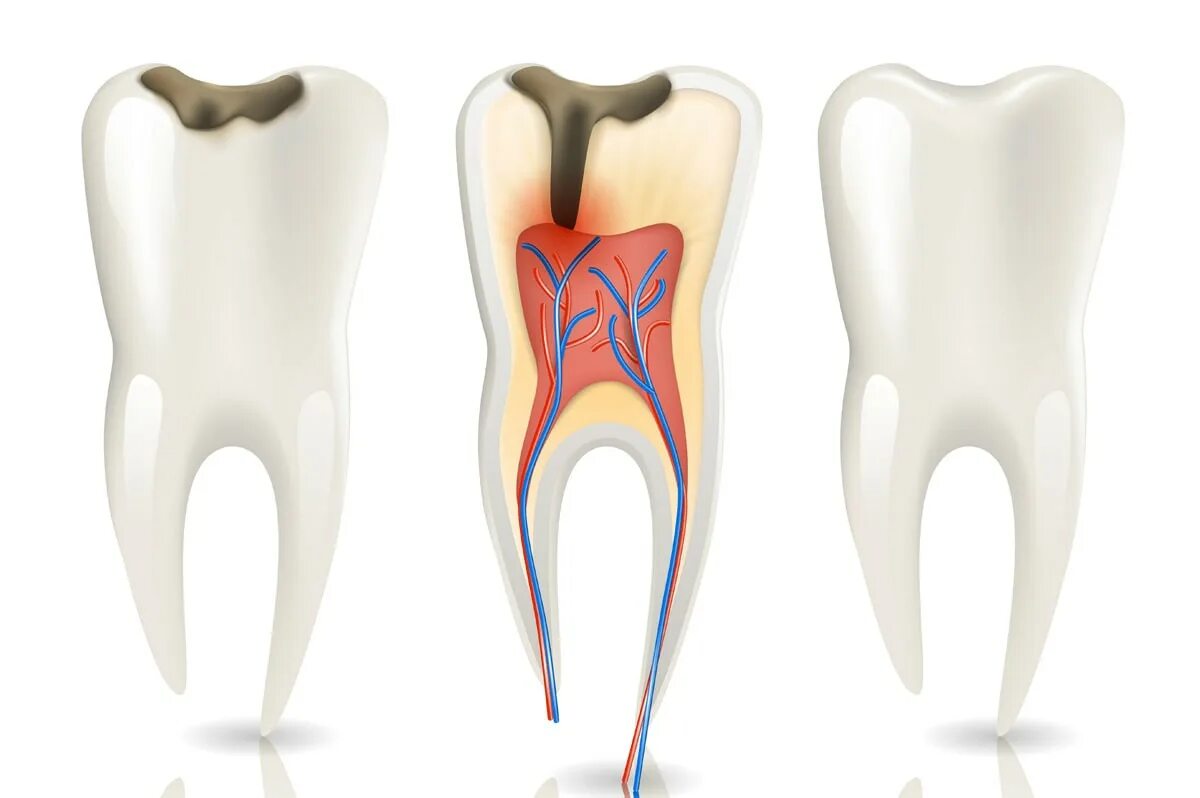

Как вылечить пульпит